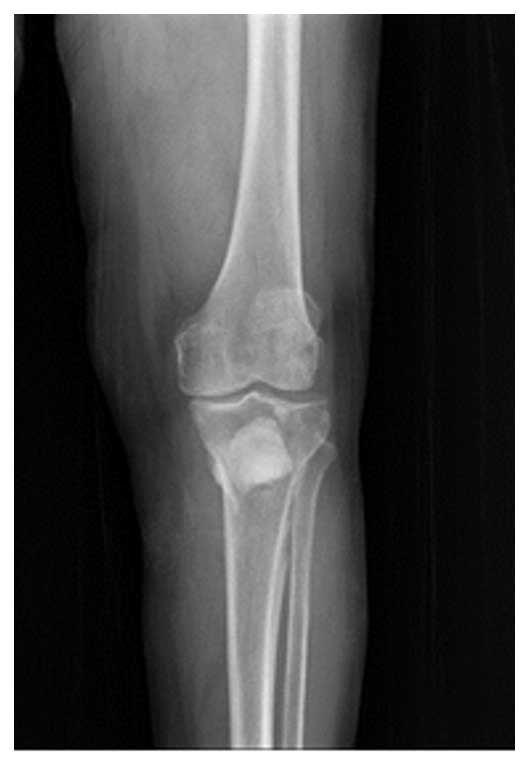

Görüntüleme yöntemlerinde sol tibia (kaval kemiği) üst uçta serviks kanseri metastazı ile uyumlu lezyon ve kemik zayıflaması saptandı. Kırık riski yüksek olarak değerlendirildi.

Ameliyat Öncesi: Röntgen ve tomografide tibia üst uç ön kısımda yeniklik, MR’da aynı bölgede tümör dokusu ve çevreleyen ödem görülmekte.